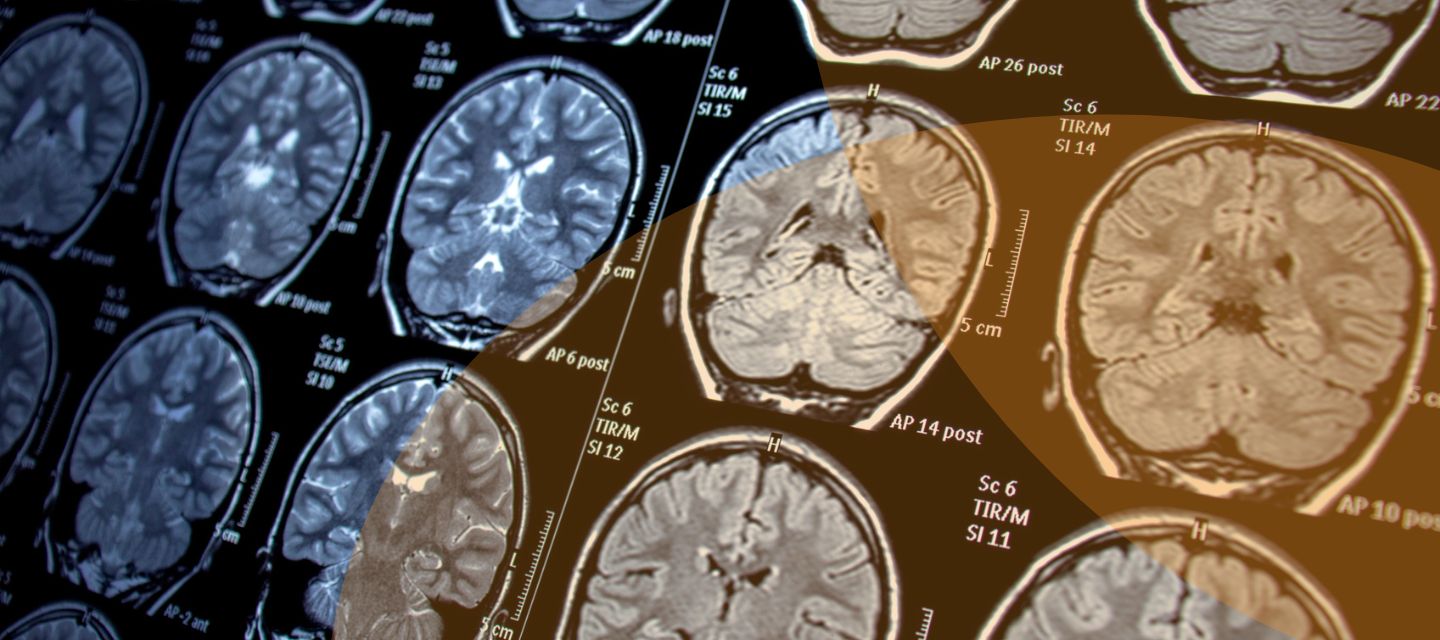

Does the 3T MRI give better quality images than the 1.5T?

The 3T scanner can produce images with better spatial resolution, however, can be more prone to artefacts. Images acquired from either 3T or 1.5T should both be of diagnostic quality in most clinical cases.